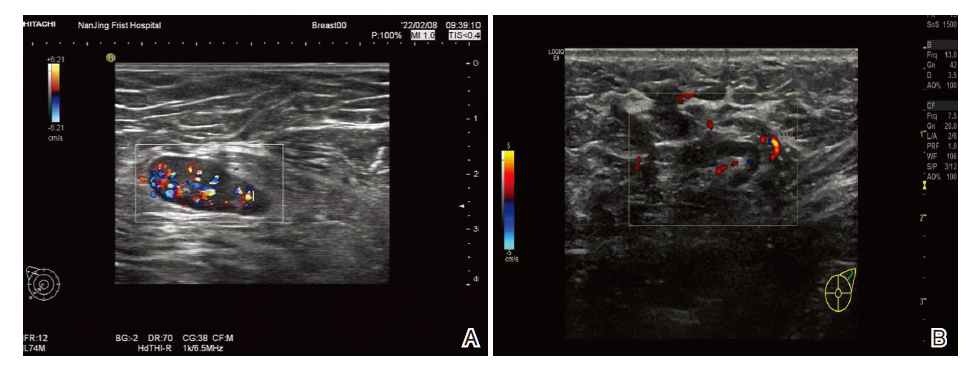

UE显示, 良性结节组患者评分以1~2分为主, 恶性结节组以3~4分为主(P< 0.05), 详见表2。两组UE图像见图2。

CDU检查显示, 良性结节组患者L/S比值明显高于恶性结节组(P< 0.05), 良性结节组患者CDFI血流特点以无血流型为主, 恶性结节组以门型为主(P< 0.05), 详见表1, 两组CDU图像见图1。